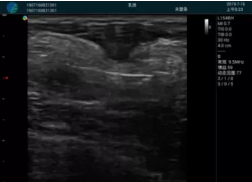

清晰顯示孕囊,通過(guò)軟件包計(jì)算孕齡7w+6d

M20實(shí)時(shí)引導(dǎo),術(shù)中清晰顯示孕囊被破壞和抽吸針的過(guò)程,清晰顯示吸引針

抽吸結(jié)束后縱切子宮,孕囊已被完全抽吸,未見(jiàn)明顯殘留

橫切子宮,發(fā)現(xiàn)右側(cè)宮腔靠近宮角處有少許脫模樣殘留

M20引導(dǎo)下,抽吸針找到右側(cè)宮角處再次清掃

二次抽吸后再次進(jìn)行超聲檢查,宮腔未見(jiàn)殘留,宮腔線(xiàn)清晰顯示